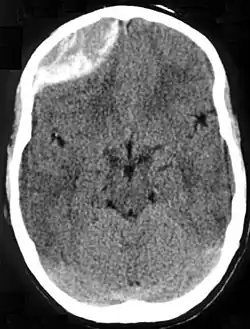

Epidural hematoma as seen on a CT scan with overlying skull fracture. Note the biconvex shaped collection of blood. There is also bruising with bleeding on the opposite side of the brain. | |

Non-contrast CT scan of a traumatic acute hematoma in the right fronto-temporal area.